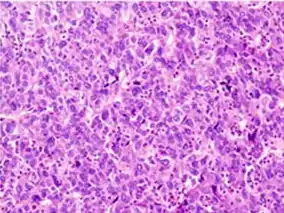

Microscopically, the four architectural and cytological types (patterns) of hepatocellular carcinoma are: fibrolamellar, pseudoglandular (adenoid), pleomorphic (giant cell), and clear cell. In well-differentiated forms, tumor cells resemble hepatocytes, form trabeculae, cords, and nests, and may contain bile pigment in the cytoplasm. In poorly differentiated forms, malignant epithelial cells are discohesive, pleomorphic, anaplastic, and giant. The tumor has a scant stroma and central necrosis because of the poor vascularization.[39] A fifth form – lymphoepithelioma like hepatocellular carcinoma – has also been described.[40][41]

Well-differentiated HCC Moderately differentiated HCC.

Moderately differentiated HCC. Poorly differentiated HCC

Poorly differentiated HCC